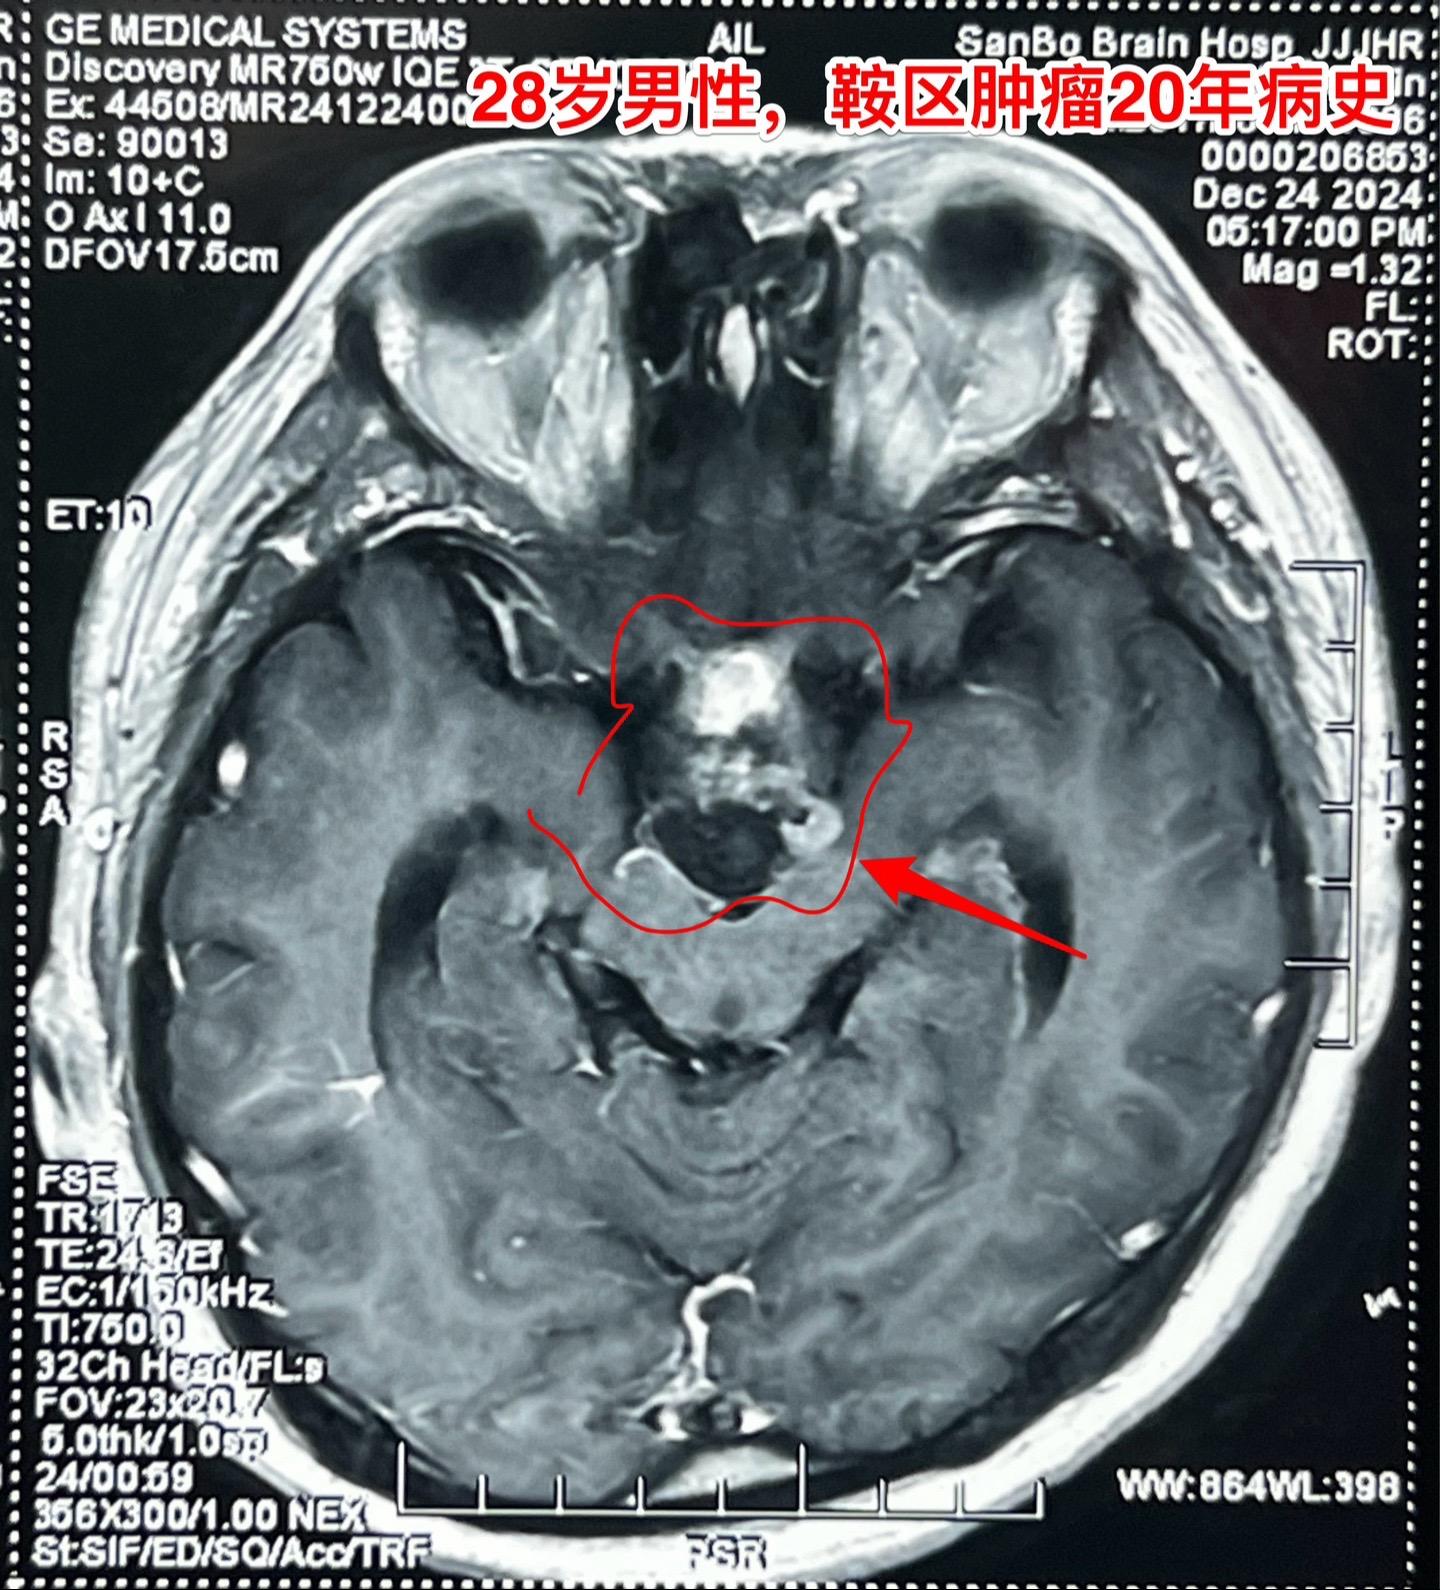

鞍区肿瘤长了20年,才下决心作手术!元旦之后的第一个鞍区肿瘤手术,怀疑是颅咽管瘤。 患者为28岁男性,20年前就发现脑部长了肿瘤,当时患者才八岁,三博脑科医院刚刚成立不久,他们就到三博脑科医院就医。因故未作手术,密切观察。 患者随后能正常读书,生长发育也还不错。后来还考上了大学,毕业后曾经在上海工作过。多次复查磁共振显示鞍区肿瘤体积在增大。而且患者也感觉视力方面出现了问题,在多个著名的医院就医过,最后下决心来找我作手术。 一月三日手术中发现肿瘤中心有钙